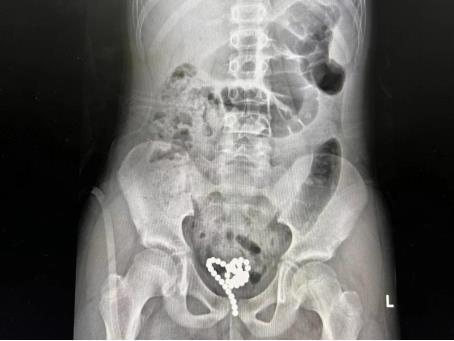

图一:患儿术前拍摄的盆腔X线

小儿泌尿系疾病亚专科主任曾青主任医师查看患儿后,考虑到患儿年龄及病情的特殊性,与泌尿外科王龙、尹光明、蒋志强等主任医师讨论后决定以微创的手术方式为患儿取出尿道膀胱内异物。手术过程中,曾青先用输尿管镜行尿道膀胱镜检,发现膀胱内有一大团形似“石榴”的彩色磁珠,磁珠之间吸附力较强,镜下难以一一分开。另外考虑到磁珠直径较粗,且患儿尿道又偏细。因此,曾青判断无法经尿道小通道取尽磁珠,立即改行膀胱造瘘,建立F24膀胱穿刺通道,助手熊伟医师用输尿管镜辅助观察视野,曾青利用子宫抓钳经膀胱穿刺通道逐一取出磁珠,通过双通道完美配合,成功为患儿取出滞留在膀胱内的全部47粒磁珠,手术用时不到1小时,术后患儿安返病房,病情稳定,复查腹部平片也再次证实膀胱内异物成功取尽。